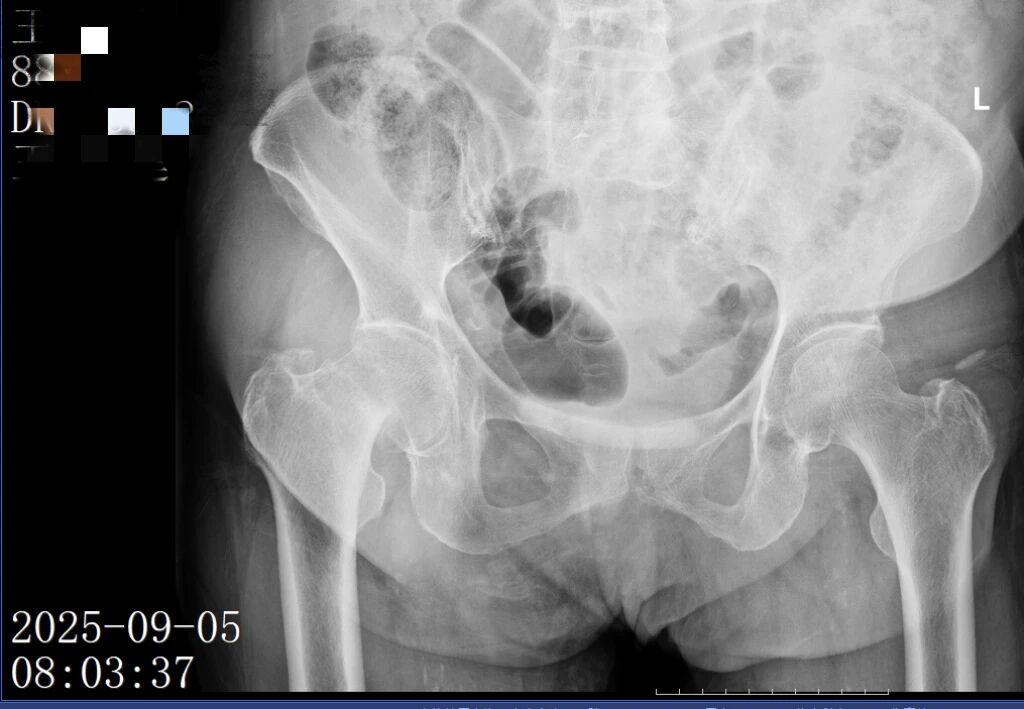

前不久,88岁的王奶奶在家中洗澡时不慎摔倒,导致右股骨颈头下型骨折。这种骨折对于超高龄老人来说异常凶险,被称为“人生最后一次骨折”。

入院后,科室立即启动多学科联合会诊,心病科、内分泌科、麻醉科、ICU、放射科等科室专家参与方案制定,经过反复讨论,确定行“右侧人工股骨头置换术”。

(▲术前)